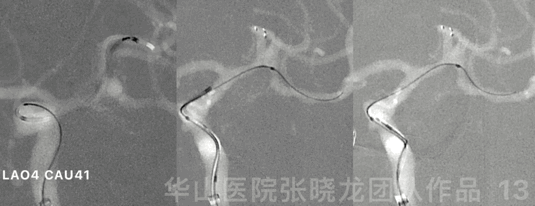

图 13 GIF. 重新选择工作角度,于瘤颈部部分释放Solitaire 4*20mm支架。直头Echelon-10微导管在微导丝导引下通过瘤颈部后轻轻回撤,微导管置于瘤腔。这过程中,3D路途显示子瘤。

图 14. 填入Target helical ultra 3mm*6cm弹簧圈。

For the superior branch, Solitaire stent was used to straighten the parent artery, then re-performed the rotation to choose a working projection for coiling.

The stent was not fully deployed, in order to advance the coiling microcatheter easier.

Stable frame to preserve the inferior branch.

采用Solitaire支架拉直大脑中动脉上干,然后旋转造影重新路途选择合适工作角度填塞弹簧圈。

为了栓塞微导管超选方便,一开始不完全支架释放。

稳定的成篮来保护大脑中动脉下干。